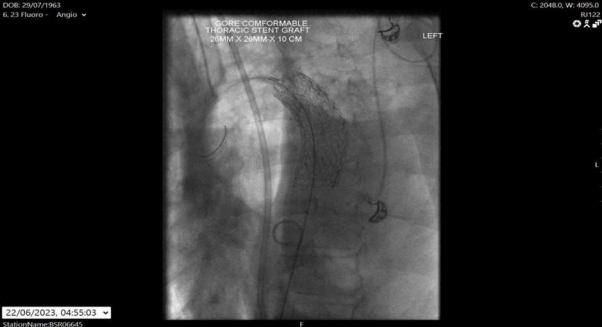

A 59-year-old patient presented to our institution with worsening moderate haemoptysis caused by a recurrent aspergilloma in his left upper lobe (fig. 1). He had a background relevant for previous pulmonary aspergilloma that had been treated with a left thoracotomy and wedge resection of the lower lobe 18 years before. He had a good performance status at his presentation. He was offered surgical treatment with a re-do left thoracotomy and upper lobe upper division segmentectomy, which was performed with no major intraoperative complications and with a blood loss of around 600 ml. He was put on Voriconazole anti fungal treatment from early and for three months post discharge. The postoperative period was initially complicated by prolonged air leaks and pneumonia. On postoperative day 15, the patient acutely developed hypotensive shock with sudden discharge of blood-stained drainage from the chest drain (around 350 ml in less than 1 hour). The chest drain was promptly clamped and, while fluid resuscitation and 3 units of blood were administered, an urgent chest radiography was obtained which confirmed a retained collection in keeping with haemothorax. At that point it was decided to perform an emergency thoracotomy and re-exploration of the pleural space. At surgery, the bleeding source was found to be coming from a 3 mm fistula connecting the lateral wall of the descending thoracic aorta to the pleural space. Since the arterial tissue around the fistula was deemed too frail to sustain direct closure with stitching, the bleeding source was initially controlled with haemostatic patches (Veriset™ Haemostatic Patch, Medtronic© Limited, Watford, UK) and packing of the pleural space with large gauze swabs. Immediately after the surgery, an angio-CT scan was performed and confirmed the presence of an irregular outpouching of the descending aorta corresponding to the known source of the bleeding (fig. 2a).

Fig. 1   Pulmonary Aspergilloma

Figure 1